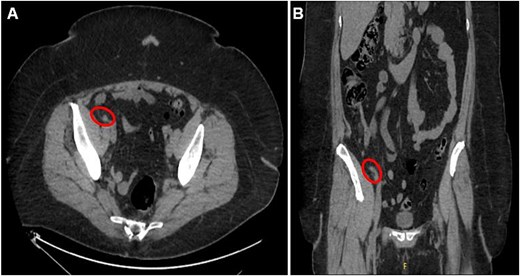

Axial (A) and coronal (B) CT abdomen and pelvis images demonstrating minimally thickened appendiceal tip measuring 7.8 mm with minimal surrounding fat stranding and no adjacent free air or fluid collection, indicating uncomplicated appendicitis.

A 56-year-old female with a history of diverticulitis, obstructive sleep apnea managed with at-home CPAP, hypertension, hyperlipidemia, obesity, asthma, gastroesophageal reflux disease, depression, and a past surgical history of cesarean section and hysterectomy presented to our institution with a four-day history of progressively worsening right lower quadrant abdominal pain associated with decreased appetite and diaphoresis. Patient denied fever, nausea, vomiting, or diarrhea, and laboratory results revealed no leukocytosis, but computed tomography (CT) scans of the abdomen and pelvis revealed minimally thickened appendiceal tip measuring 7.8 mm with surrounding fat stranding suggesting early acute uncomplicated appendicitis (Fig. 1A and B). Given these imaging findings and significant right lower quadrant tenderness to palpation on physical examination, the patient was admitted and subsequently underwent a laparoscopic appendectomy without any intraoperative complications. The patient’s postoperative course was uncomplicated and was eventually discharged on post-operative day 1. Pathological examination of the removed appendix from the operation stained positive for markers PAX8, ER, PR (focal), and CK7 and negatively for markers CD10, CDX2, and CK20, indicating non-cancerous ectopic fallopian tube-type ciliated epithelial tissue consistent with endosalpingiosis of the appendix (Fig. 2A and B, Fig. 3A–E).

Imaging in the presented case demonstrated minimal fat stranding with minimal thickening of the appendiceal tip, suggesting early findings of appendicitis which prompted surgical intervention. This finding in fact contradicts some of the previous literature which proposed a lack of inflammatory processes evident on CT imaging [2]. Additionally, pathological evaluation confirming the complete absence of acute appendicitis suggests that appendiceal endosalpingiosis may induce some inflammatory response visible on imaging, although quite minimal and of unknown significance.